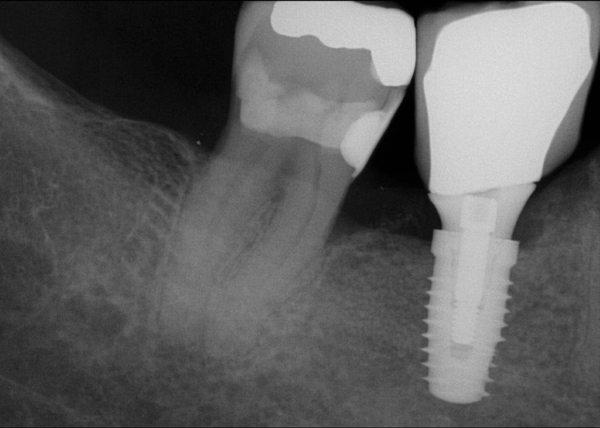

Fig 15. (Case 3) Radiograph of tooth No. 19, which had a hopeless prognosis.

Figure 15

Fig 16. Radiograph of extraction socket. Buccal and lingual plates were defective.

Figure 16